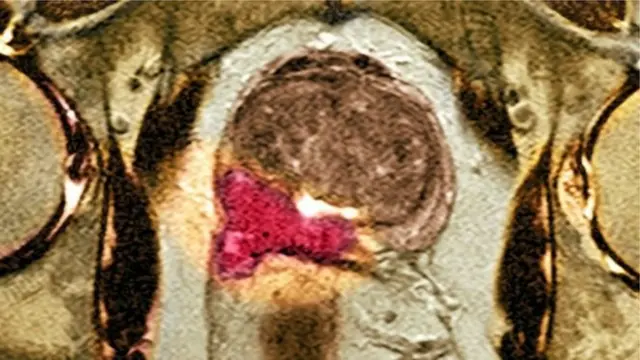

د پروستات وده

پروستات سرطان تل وژونکی نه وي - ځینې غوټې یا تیومر یې دومره ورو وده کوي چې ستونزه نه پېښوي - د لرې کولو اړتیا یې نه وي او یوازې کېدلی شي وڅارل شي.

ننګونه په سړو کې د پروستات سرطان د هغې بڼې په وخت مالومول او مخنیوی دی چې په خورا چټکۍ وده کوي او کېدلی شي وژونکې وي.

دم ګړۍ چې کوم طبي معاینات شته لکه د وینې ازموینه یا بیاپسې - تل په دې نه توانېږي چې اټکل وکړي د سرطان کومه بڼه ده او څومره به خطرناکه وي.